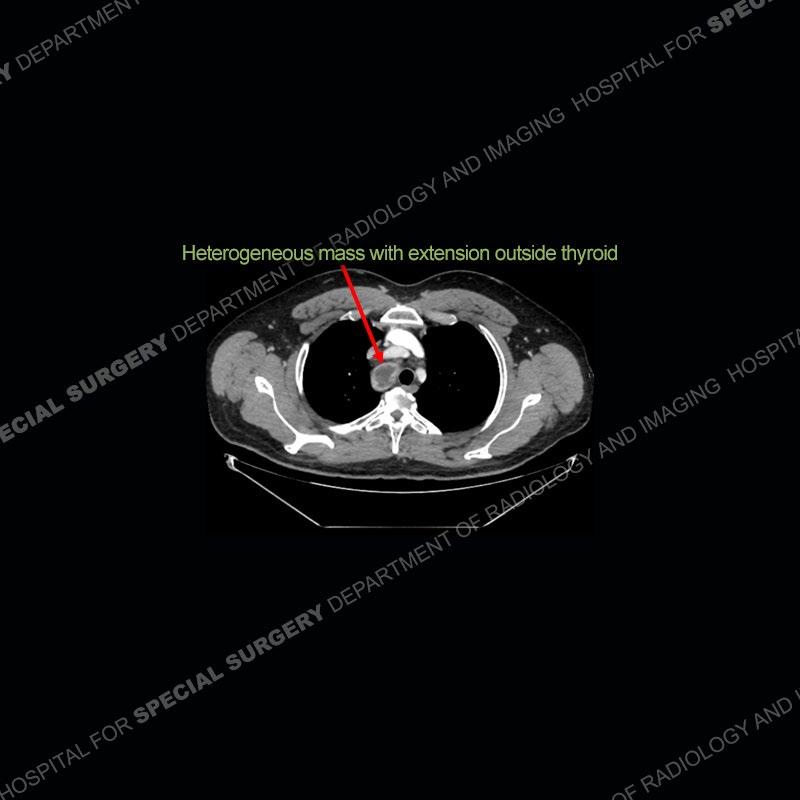

The chest radiographs demonstrate a leftward deviation of the trachea. CT images demonstrate a large, somewhat heterogeneous mass of the thyroid that extends outside the confines of the thyroid tissue. There is a subtle, enhancing soft tissue mass of the proximal right humerus. Slightly prominent mediastinal lymph nodes are present with additionally, multiple supraclavicular lymph nodes.

Although not strictly a part of the evaluation of an “incidental” thyroid lesion, evaluation of the adjacent lymph nodes and bony structures can also be quite important. In this case, there is an enhancing mass of the right humerus. This is very subtle and can only really be recognized by evaluating the density of the bone. Typicaly marrow will have a fatty density or nearly fluid density. As the density, as in this case, approaches soft tissue an infiltrative process must be entertained. Thyroid mets are markedly vascular accounting for the areas of enhancement of the humeral mass. The mediastinal and supraclavicular lymph nodes although not individually enlarged, should raise suspicion of an underlying inflammatory/neoplastic process.